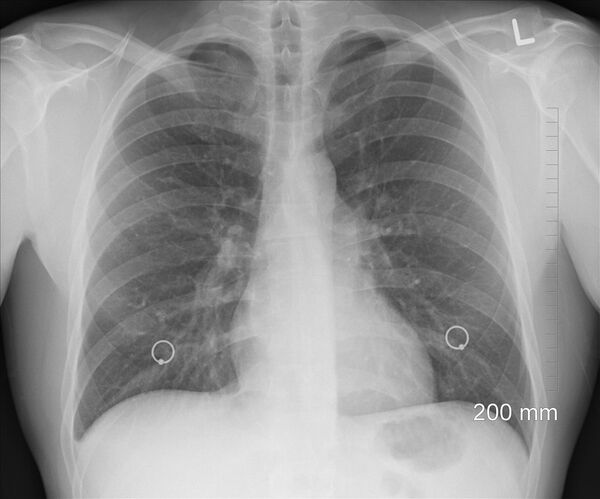

План је укључивао ЦТ грудног коша, тродимензионално скенирање плућа које открива детаљне слике. Проучавањем хиљада таквих слика, алгоритам ће научити дешифровати да ли је узрок упале плућа ковид-19 или нешто уобичајено, попут грипа, за "Wired" пише Грегори Барбер.

Како је вирус у фебруару почео да се шири САД-ом, идеја је постала обећавајућа. С обзиром да је недостајало конвенционалних тестова, био је то начин да се више људи прегледа у што краћем року. Здравствени радници, међутим, нису били сигурни у ово решење. Иако су различити дијагностички алгоритми већ добили одобрење америчке Агенције за храну и лекове, за фрактуре шаке, очне болести, рак дојке , обично су за њихов развој биле потребне године. Коришћени су у различитим болницама с различитим пацијентима, испитани су њихови недостаци и темељно су тестирани.

Постоји ли о новом вирусу довољно података да би се једна упала плућа заиста разликовала од друге? Што је с благим случајевима, при којима оштећења можда нису тако видљива? Пандемија није чекала да се појаве одговори, али медицина би морала, пише Барбер.

Крајем марта, Уједињене Нације и Светска здравствена организација објавили су извештај у коме се испитивао ЦТ грудног коша и низ других апликација вештачке интелигенције у борби против ковида-19. Благо бирократска процена била је да неколико пројеката има "оперативну зрелост".